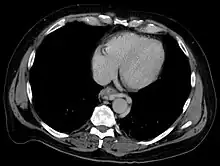

| Gastroscopy image of esophageal varices with prominent cherry-red spots and wale signs | |